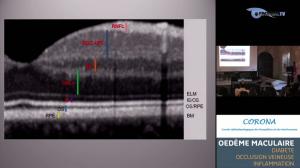

Les oedèmes maculaires dans les autres pathologies rétiniennes

Par : Dr Isabelle Meunier - Montpellier